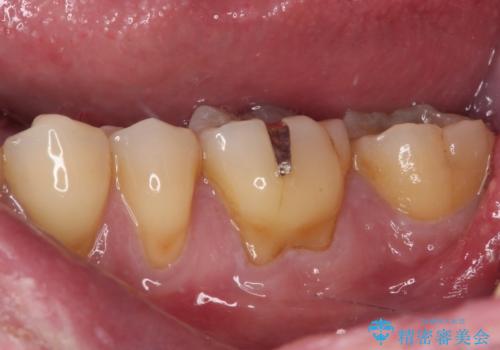

後方は歯肉内にまで虫歯が及んでいたため、歯肉の一部を切除して、クラウンとの境目を明示して処置を行いました。

クラウン装着後には、来院時に気になさっていた歯肉の腫れが解決され、快適に生活を送れるようになりました。